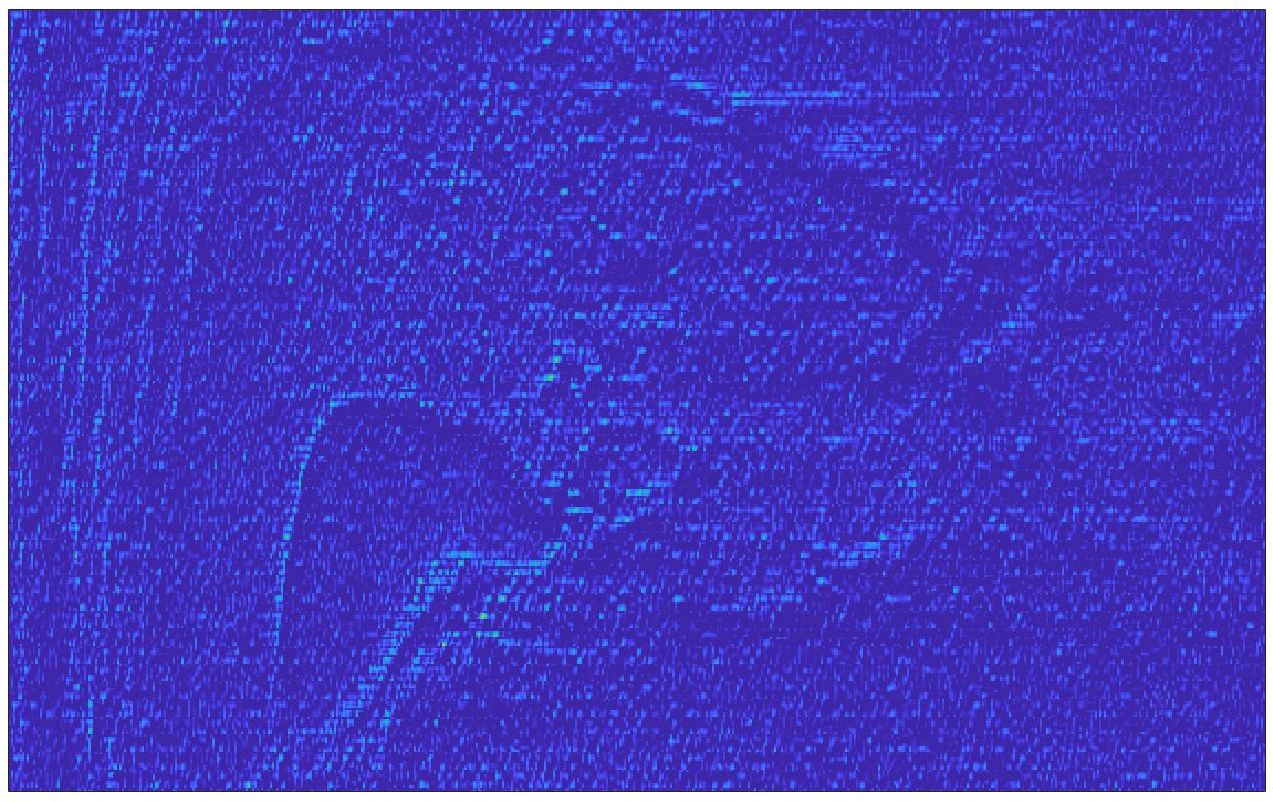

We train each learning-based network (custom-WDSR) with 1.5K images, where the input is the outcome of the selected up-sampling method (i.e., Cubic convolution), and the target is the original high-resolution image. Indeed, input and target images have the same resolution, as the reconstruction of the missing lines has been already performed by Cubic convolution. Figs. 3, 4, and 5 show the results of the network prediction, compared with the input and the target images. Target images correspond to spatial high-resolution images; input images are the outcome of the up-sampling interpolation, which is applied to spatial low-resolution images (i.e., the down-sampling along the lateral direction of high-resolution images); prediction images represent the output of the neural network.

Our framework visually improves the results, in terms of blurring and artefacts. This result is more evident in the magnification of the ear of the foetus (Fig. 3), the mitral valve (Fig. 4), and the mass edges (Fig. 5). Fig. 6 shows the error image of the three anatomical districts with both 2X and 4X up-sampling factors, with the maximum error in the scale . The error is more evident in the contours of the anatomical structures; moreover, the abdominal district shows a smaller error than the cardiac and obstetric ones. We underline that the view for each image is scaled to its maximum, to improve the visualisation of the error.